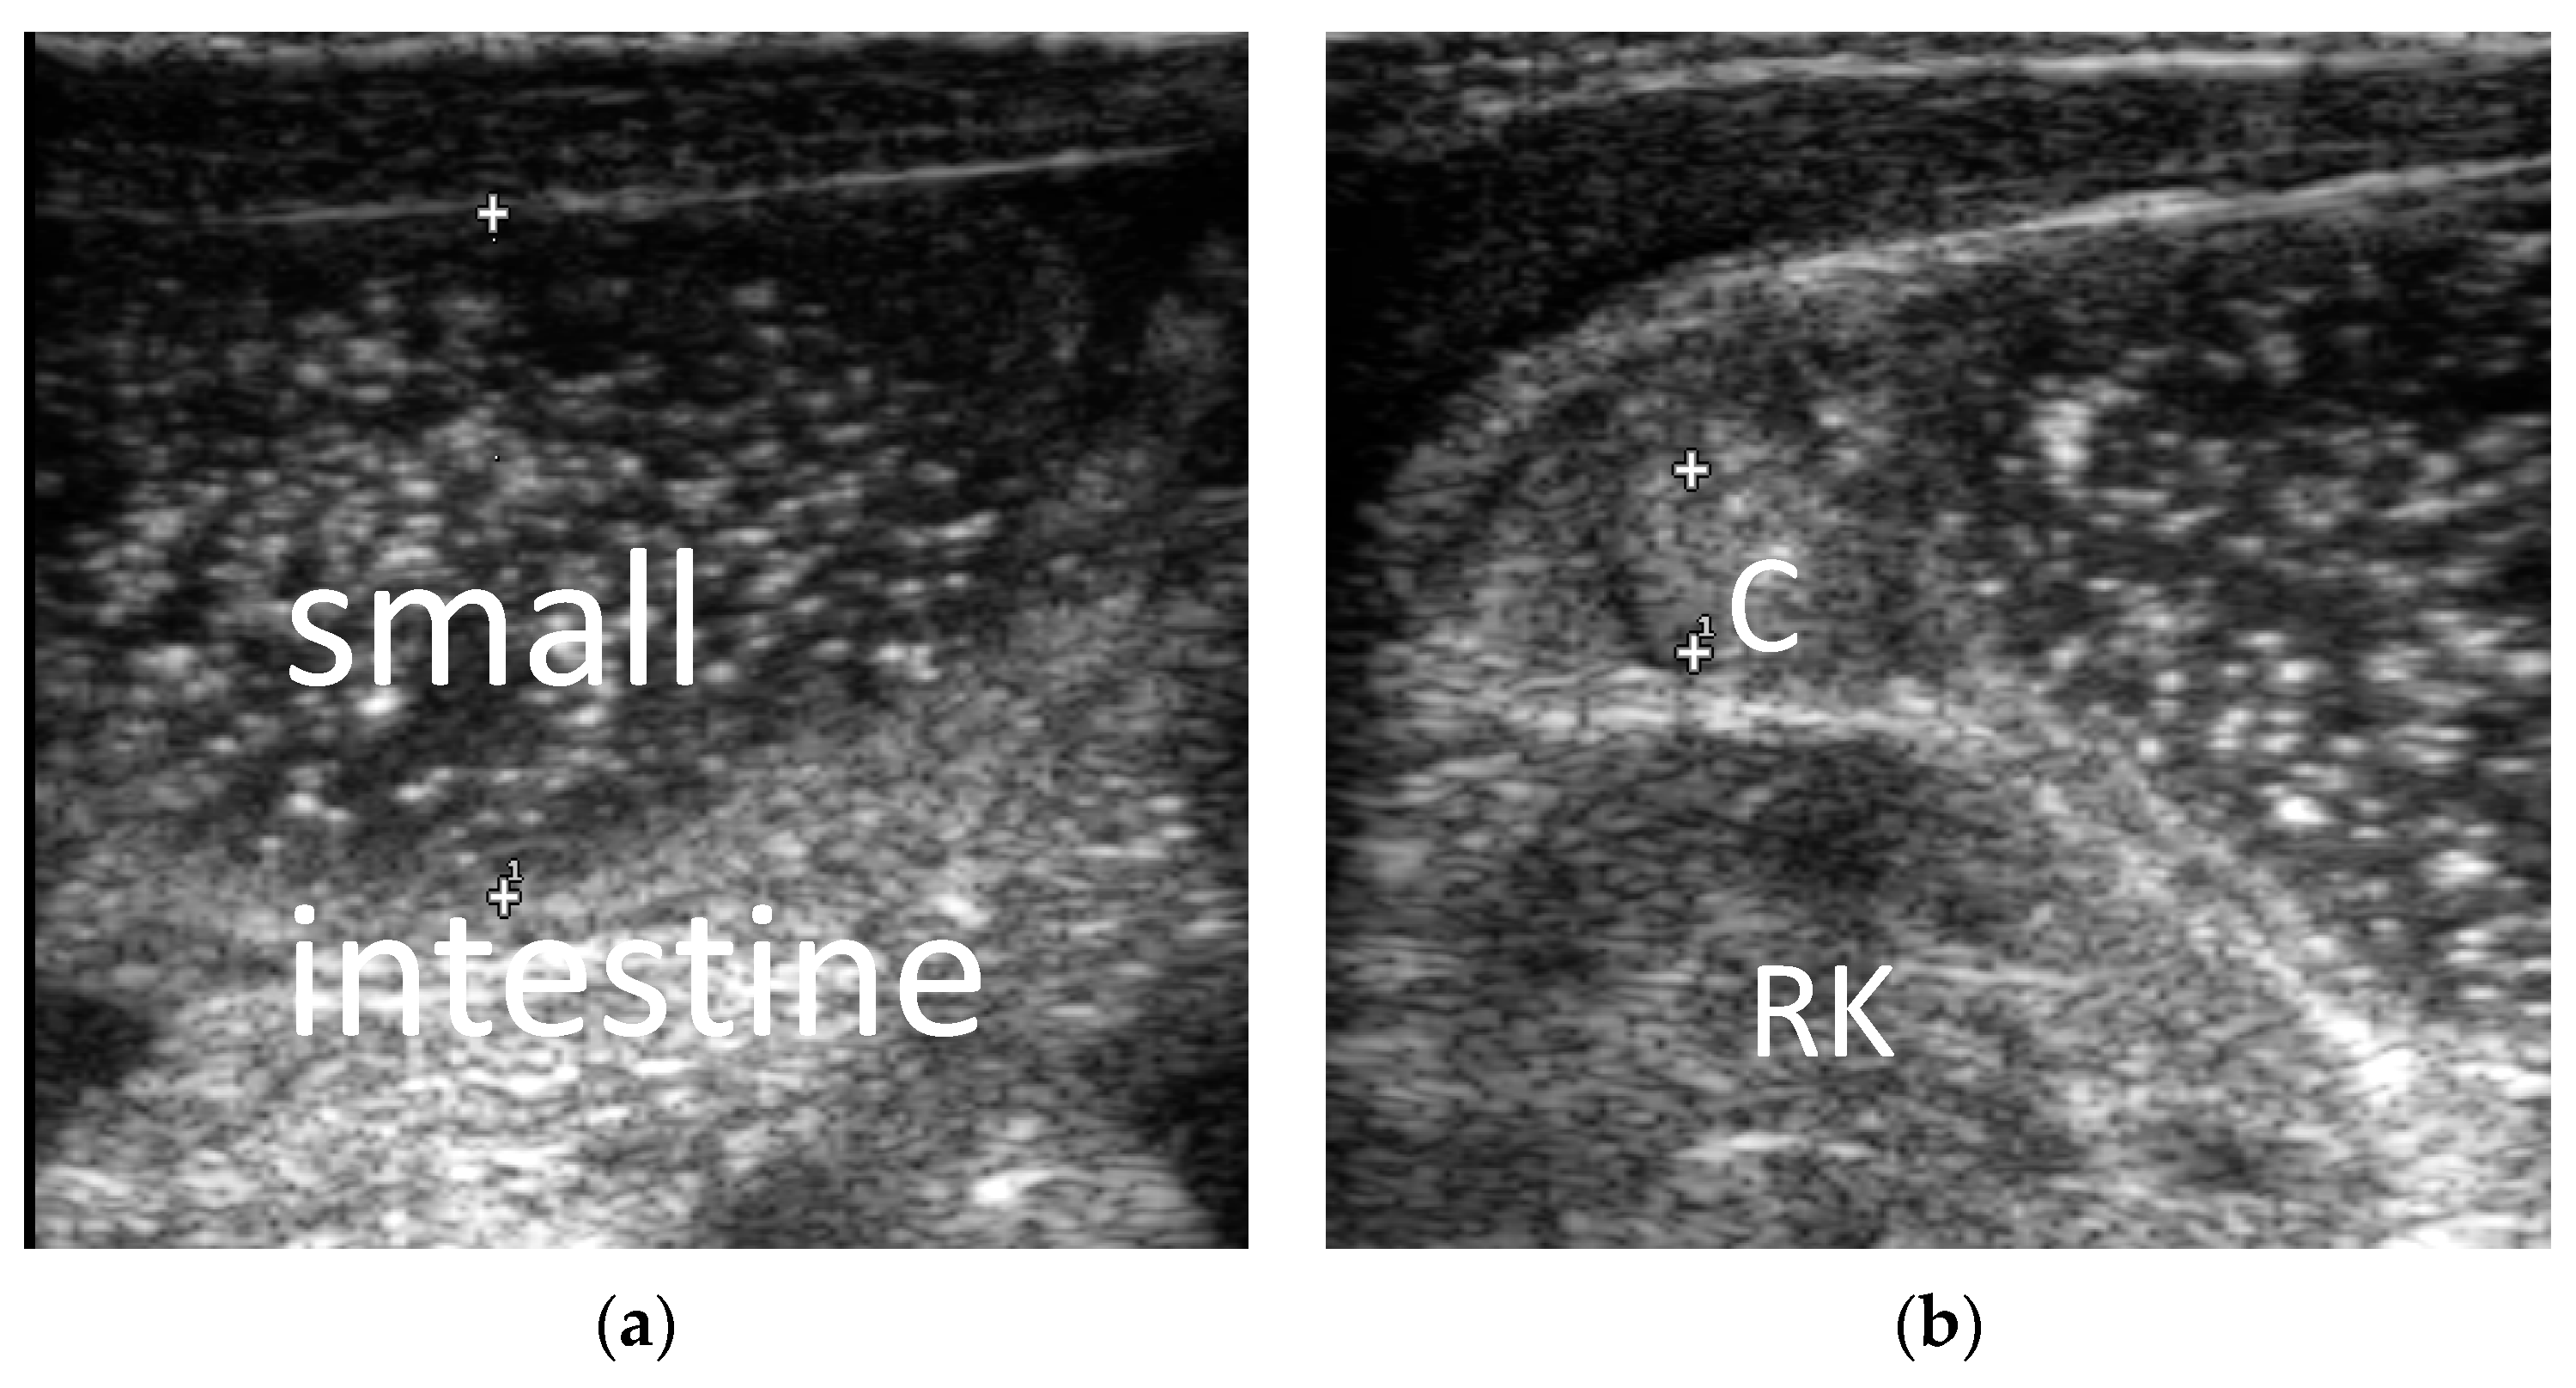

From www.mdpi.com

Diagnostics Free FullText Ultrasonic Diagnosis of Intestinal Diagnostic Tests For Intestinal Obstruction Outline the evaluation in a patient with bowel obstruction. Intestinal obstruction is a blockage that keeps food or liquid from passing through your small intestine or large intestine (colon). Ct findings in patients with intestinal obstruction include. You may need a complete blood count and. They may use a stethoscope to listen for bowel sounds that signal an obstruction. Several. Diagnostic Tests For Intestinal Obstruction.